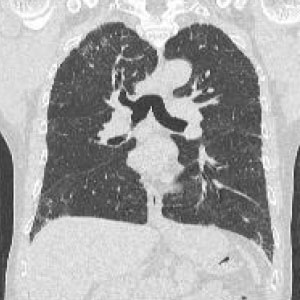

CTとはComputed Tomography(コンピュータ断層撮影)の略です。

検査はエックス線を利用し体の断面を撮影します。頭から全身に至るまで様々な検査が可能です。当院では80列マルチスライスCTを導入し短時間で低被ばくかつ高精細な検査が可能となりました。

脳血管障害、脳腫瘍、頭部外傷、顔面骨骨折、副鼻腔炎、甲状腺疾患、肺炎、肺がん、食道がん、肺塞栓、縦隔疾患、消化管疾患・がん・炎症、泌尿器疾患、婦人科疾患、大動脈瘤、脊椎骨折、骨盤骨折、上下四肢骨折、下肢動静脈疾患など